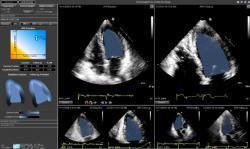

Based on the ASE guidelines, the suite includes automated linear, area and volumetric measurements designed to save time and improve standardization in echo analysis. Developed specifically for the clinical environment, EchoInsight is vendor-neutral and now includes an automated measurement suite, practical application-specific strain imaging, and rapid study comparison and trending for comprehensive assessment and patient monitoring in echo.

- “Relation between Left Atrial (LA) Deformation Imaging in Varying Degrees of Left Ventricular (LV) Diastolic Dysfunction (DD),” presented by Amita Singh, M.D., Karima Addetia, Roberto Lang, et al., from the University of Chicago Medicine. In this study 100 age-matched patients with left ventricular ejection fraction (LVEF) >50 percent and no significant valvulopathy were assessed, including: 25 normal subjects (NL) and three groups of 25 patients each with grades 1, 2 and 3 diastolic dysfunction (DD), as defined by ASE guidelines. Mitral inflow E velocity, E-wave deceleration time, A-velocity, lateral and medial mitral annular E’ velocities, E/(mean E’), LA volumes (biplane Simpson), and 2-D speckle tracking derived LA longitudinal strain (EchoInsight) were measured throughout the cardiac cycle (and atrial stiffness defined as (E/E’/peak LA strain)). The study concluded in subjects with LV DD and preserved EF, changes in LA deformation and stiffness with worsening DD reflect a progressive decline in LA function, which is not as easily identified by conventional Doppler and LA volume measurements.

- “Left Atrial Strain Predicts Atrial Fibrillation Recurrence in Patients with Persistent Atrial Fibrillation and Preserved Ejection Fraction Treated With Catheter Ablation,” presented by Mislav Vrsalovic, Theodore Kolias, et al. from University of Michigan. 92 patients with persistent atrial fibrillation (AF) and preserved EF underwent first catheter ablation (CA) and echo ≤ 30 days prior to CA. Left atrial and ventricular global longitudinal strains (GLS) were measured with 2-D speckle tracking (EchoInsight), and patients were followed for AF recurrence. The study concluded left atrial GLS is a strong and independent predictor of AF recurrence after first CA therapy in patients with persistent AF and preserved EF.

- “Echocardiographic Evaluation Of Right Ventricular Function in Patients with McConnell’s Sign: The Added Benefits of Right Ventricular Free Wall Strain,” presented by Anuj Mediratta, Karima Addetia, Roberto Lang, et al. from University of Chicago Medicine. 156 transthoracic echocardiogram (TTE) studies were reviewed with McConnell’s sign (MS) and a diagnostic study (computed tomography or V/Q scan) was given within 48 hours to evaluate for acute pulmonary embolism (PE). Echo images were analyzed with EchoInsight to measure right ventricular (RV) fractional area change (FAC), tricuspid annular plane systolic excursion (TAPSE), early tricuspid annular velocity S’ and 2-D speckle-tracking derived RV free-wall longitudinal strain (LS) and segmental free-wall strain of apex, mid and basal RV. The study concluded that patients with MS have reduced global RV free wall strain, segmental strain including the apex. Qualitative assumption of normal RV apical function in MS is likely related more to left ventricular apex contractility with tethering of the RV apex rather than normal RV apex function.